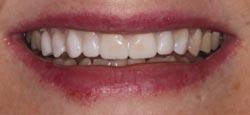

1. What injury can be diagnosed from the teledentistry photo (below), and what is the importance of timely surgery attendance for this type of injury?